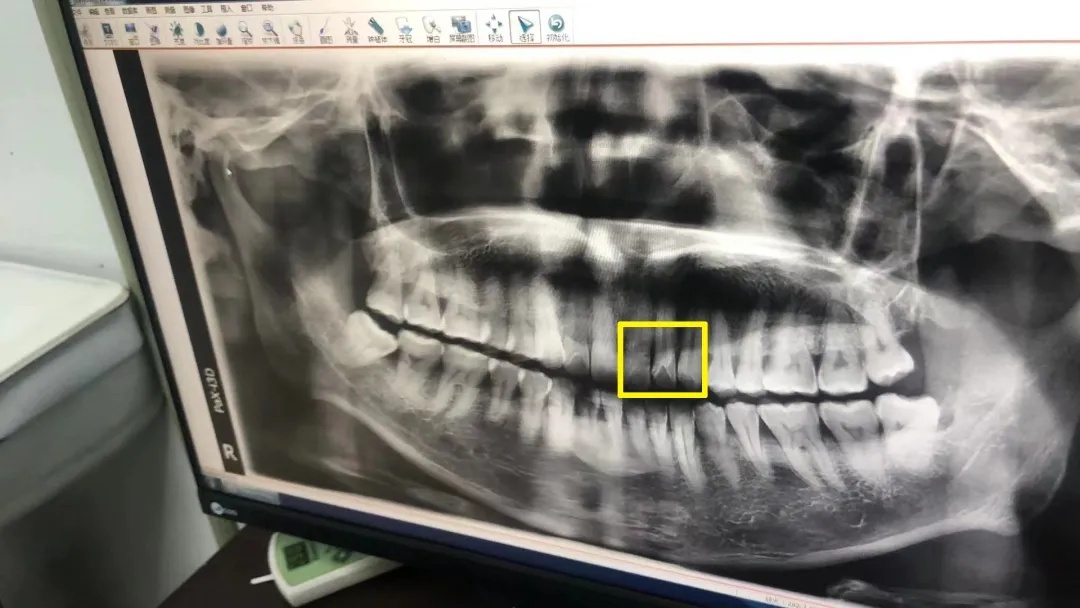

才发现牙齿断了3颗

嘴巴也缝了8针